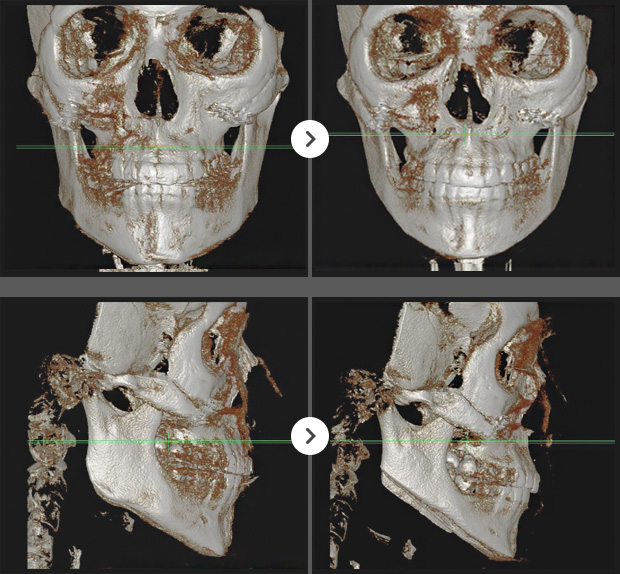

CT BEFORE & AFTER

3D광대, 긴곡선사각턱, 앞턱V절골(3mm전진)

긴곡선사각턱,앞턱V절골(길이축소)